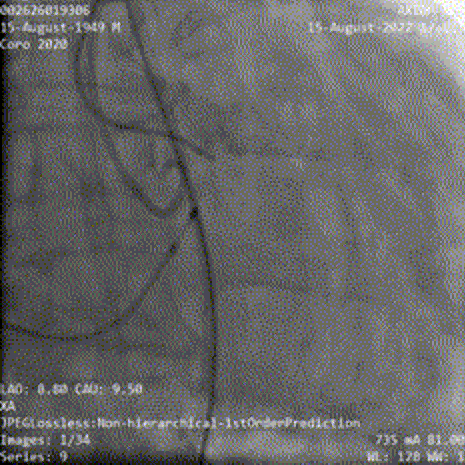

术前行冠状动脉造影提示左右冠状动脉未见有意义狭窄;

左冠造影

右冠造影